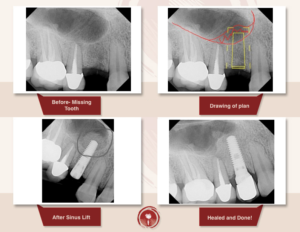

Операція синус ліфтинг

Це хірургічна операція по нарощуванню кісткової тканини в бічних відділах верхньої щелепи, для якісного встановлення імплантатів.

Як одна з методик автокісткової пластики, синус ліфтинг щелепи дозволяє відновити необхідний обсяг кісткової тканини альвеолярного відростка в передбачуваній області фіксації імплантату, за рахунок зменшення простору верхньощелепної (гайморової) пазухи.

При більшій пневматизації показаний закритий синус ліфтинг або м’який (soft) з доступом через канал ложа імплантату.

При наявному обсязі кісткової тканини менше 5 мм показаний відкритий синус ліфтинг – пластика дна верхньощелепної пазухи з доступом-перфорацією передньої стінки пазухи.